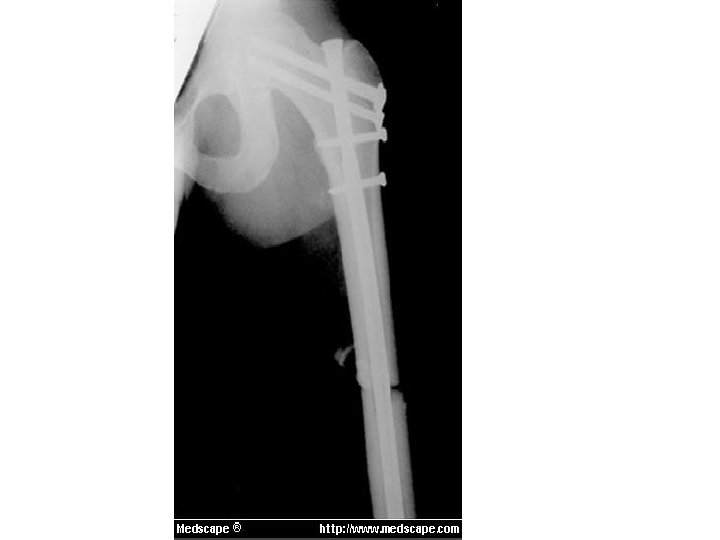

Interlocking nailing • Nail is introduced in the medullary cavity. • The screws are passed from the cortex through the holes in the nail.

Closed Intramedullary nailing Advantages • Inside the medullary cavity, so more stable than plate, less exposure required. • Fracture hematoma is maintained. • Early use of limb, restoration of length and alignment, rapid union and low re-fracture rates are the advantages.